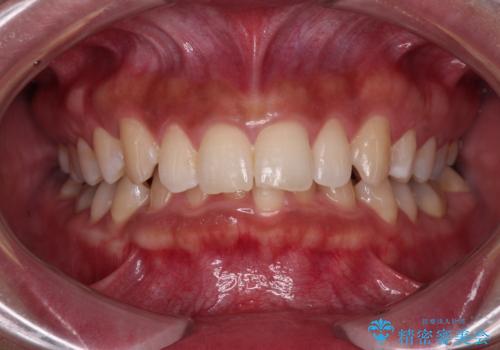

前歯の隙間とへこみが舌で触ると気になる|矯正治療は絶対にしたくない|抜歯即時インプラント+オールセラミッククラウンで審美修復

[ セラミック治療 ] 前歯の見た目を改善したい